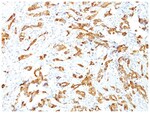

HSP27 Monoclonal specifically detects HSP27 in Human, Mouse, Rat, Chicken, Chimpanzee, Monkey, Sheep samples. It is validated for Western Blot, Flow Cytometry, Immunohistochemistry, Immunocytochemistry/Immunofluorescence, Immunohistochemistry-Paraffin.Specifications

| This MAb reacts specifically with heat shock protein HSP27 in human and monkey tissues and cell lines such as MCF-7. HSP27, also referred to as the Estrogen-Regulated 24K protein and HSP28, is one of several small heat shock proteins produced by all organisms studied. HSP27 synthesis is induced by elevated temperature, as well as by estrogen in hormone responsive cells. Interestingly, human HSP27 also shares greater than 50% homology with low molecular weight Drosophila HSPs and mammalian alpha-crystalline lens protein. Because of the estrogen responsive nature of HSP27, this protein has been studied extensively in human estrogen responsive tissues such as cervix, endometrium and breast tissue. Therefore HSP27 may be useful in classifying various hormone sensitive tumors. |